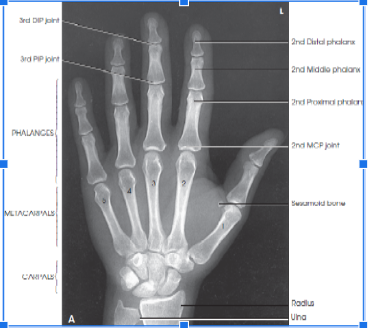

anatomy from fingertips to distal radius and ulna

Evaluation criteria - What should be visible on the metacarpal and phalangeal bodies?

equal concavity of the metacarpal and phalangeal bodies

equal amount of soft tissue on both sides of the phalanges

equal distance between the metacarpal heads

evaluation criteria - what should be visible in the center of each distal phalanx?

the nail

evaluation criteria - What joint spaces should be visible in a PA hand image and what does it indicate?

MCP and IP joints. It indicates that the hand is flat on the IR